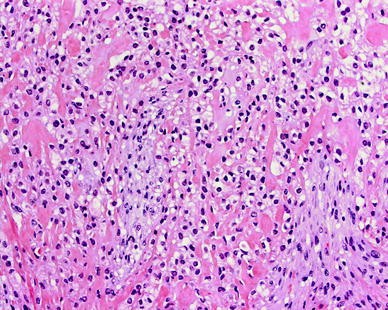

7. Hyalinizing Clear Cell Carcinoma

- Number of People Afflicted Yearly: about 51 cases ever reported

- Area of Body Affected: Salivary glands, tongue, or palate

- Is it Treatable?: Yes

- Survival Rate: High (percentage unspecified)

In 1994, the Hyalinizing Clear Cell Carcinoma was categorized as a low-grade tumor of the salivary glands for the first time. Approximately 11 cases of Hyalinizing Clear Cell Carcinoma were described while the initial case study was being conducted.

In the time since then, approximately forty further cases of hyalinizing clear cell carcinoma have been documented. This takes the total number of instances of Hyalinizing Clear Cell Carcinoma up to over 50, making it the rarest form of cancer that can occur anywhere in the globe.

Based on the cases that have been documented, medical professionals now understand that women are more likely to be diagnosed with Hyalinizing Clear Cell Carcinoma.

Hyalinizing Clear Cell Carcinoma is an extremely uncommon form of malignant salivary gland tumor that accounts for around 1% of all intra-oral salivary gland tumors.

Surgery is an option for treating this particular form of cancer, and people who undergo treatment typically make a full recovery.